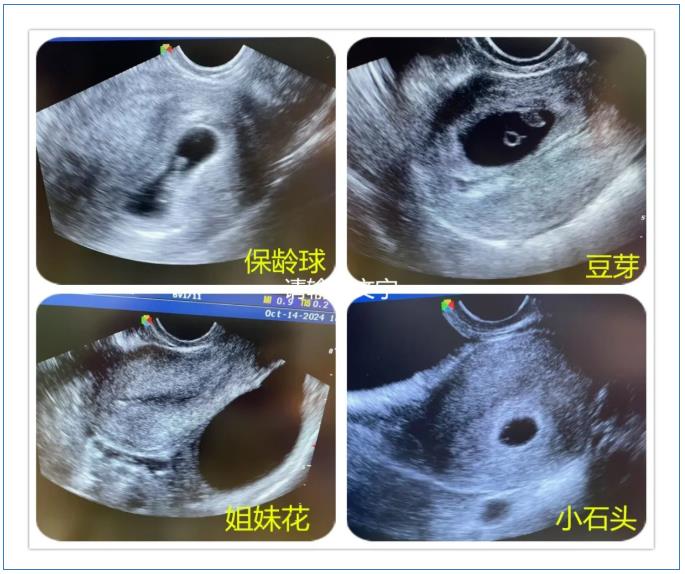

当超声探头的凝胶在腹部晕开涟漪,显示屏上的光斑便化作生命的星图。那些不足指甲盖大的孕囊,有的像春日里第一颗露珠,有的像蓝天下的云朵,还有的像时间的沙漏……“小豌豆”是六周的胚芽,绒毛膜正在形成玫瑰花瓣般的皱褶;“蒲公英”是八周的胚胎,羊膜腔里漂浮着绒毛的丝絮;“星星是意外停育的孕囊,却依然保持着完美的图形。

无影灯下,金属器械碰撞的清脆声中,总流淌着温柔的诗句。麻醉师在推注丙泊酚前会轻声念诵:“你原是银河的星子,偶然投影在春天的湖”,让患者在美妙的意象中沉入梦境。最特别的还是胚胎病理标本瓶,每个透明容器上都贴着名字:云朵、小水滴、水晶公主、沙漏、天平、创可贴……将无法言说的遗憾转化成语言的琥珀。它们用独特的存在方式告诉我们:生命是一段奇妙的旅程,每一段经历都值得我们珍惜,纵然逝去,也要留下温柔的印记。

请相信,当你为每一个孕囊轻轻唤作一个名字,它们便不再是冰冷的数据,而是有了温度的存在——那一刻,它们分外美丽,而你也不再孤单。